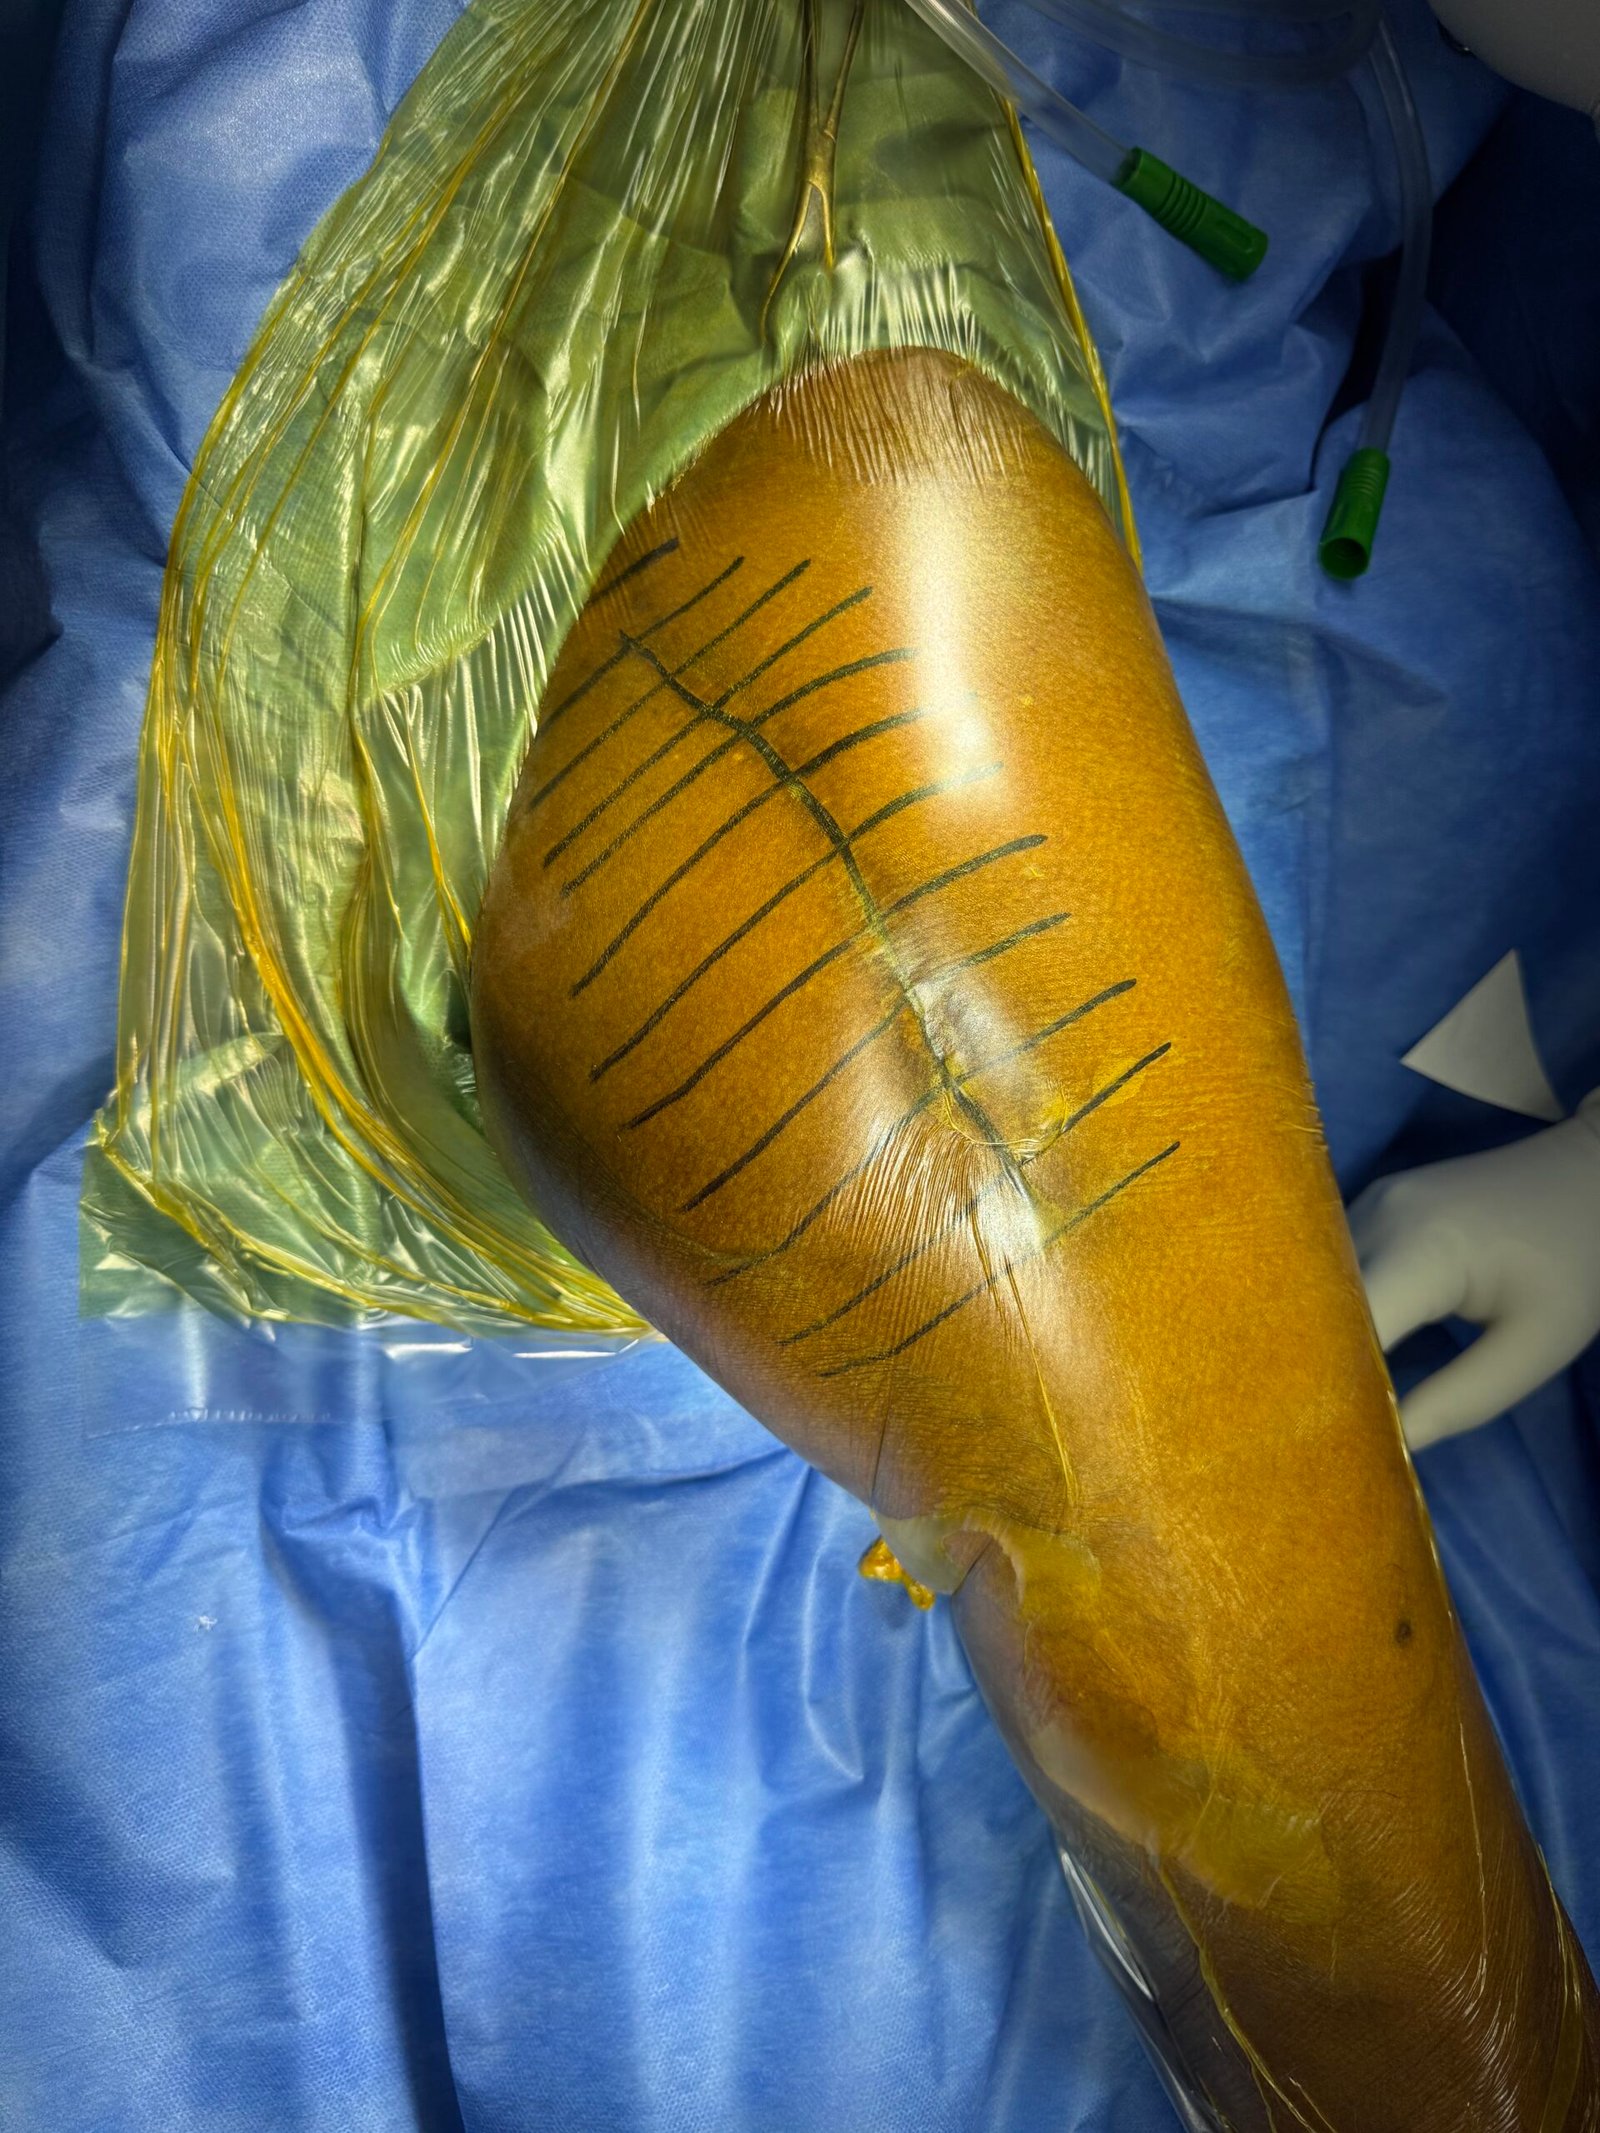

Draping